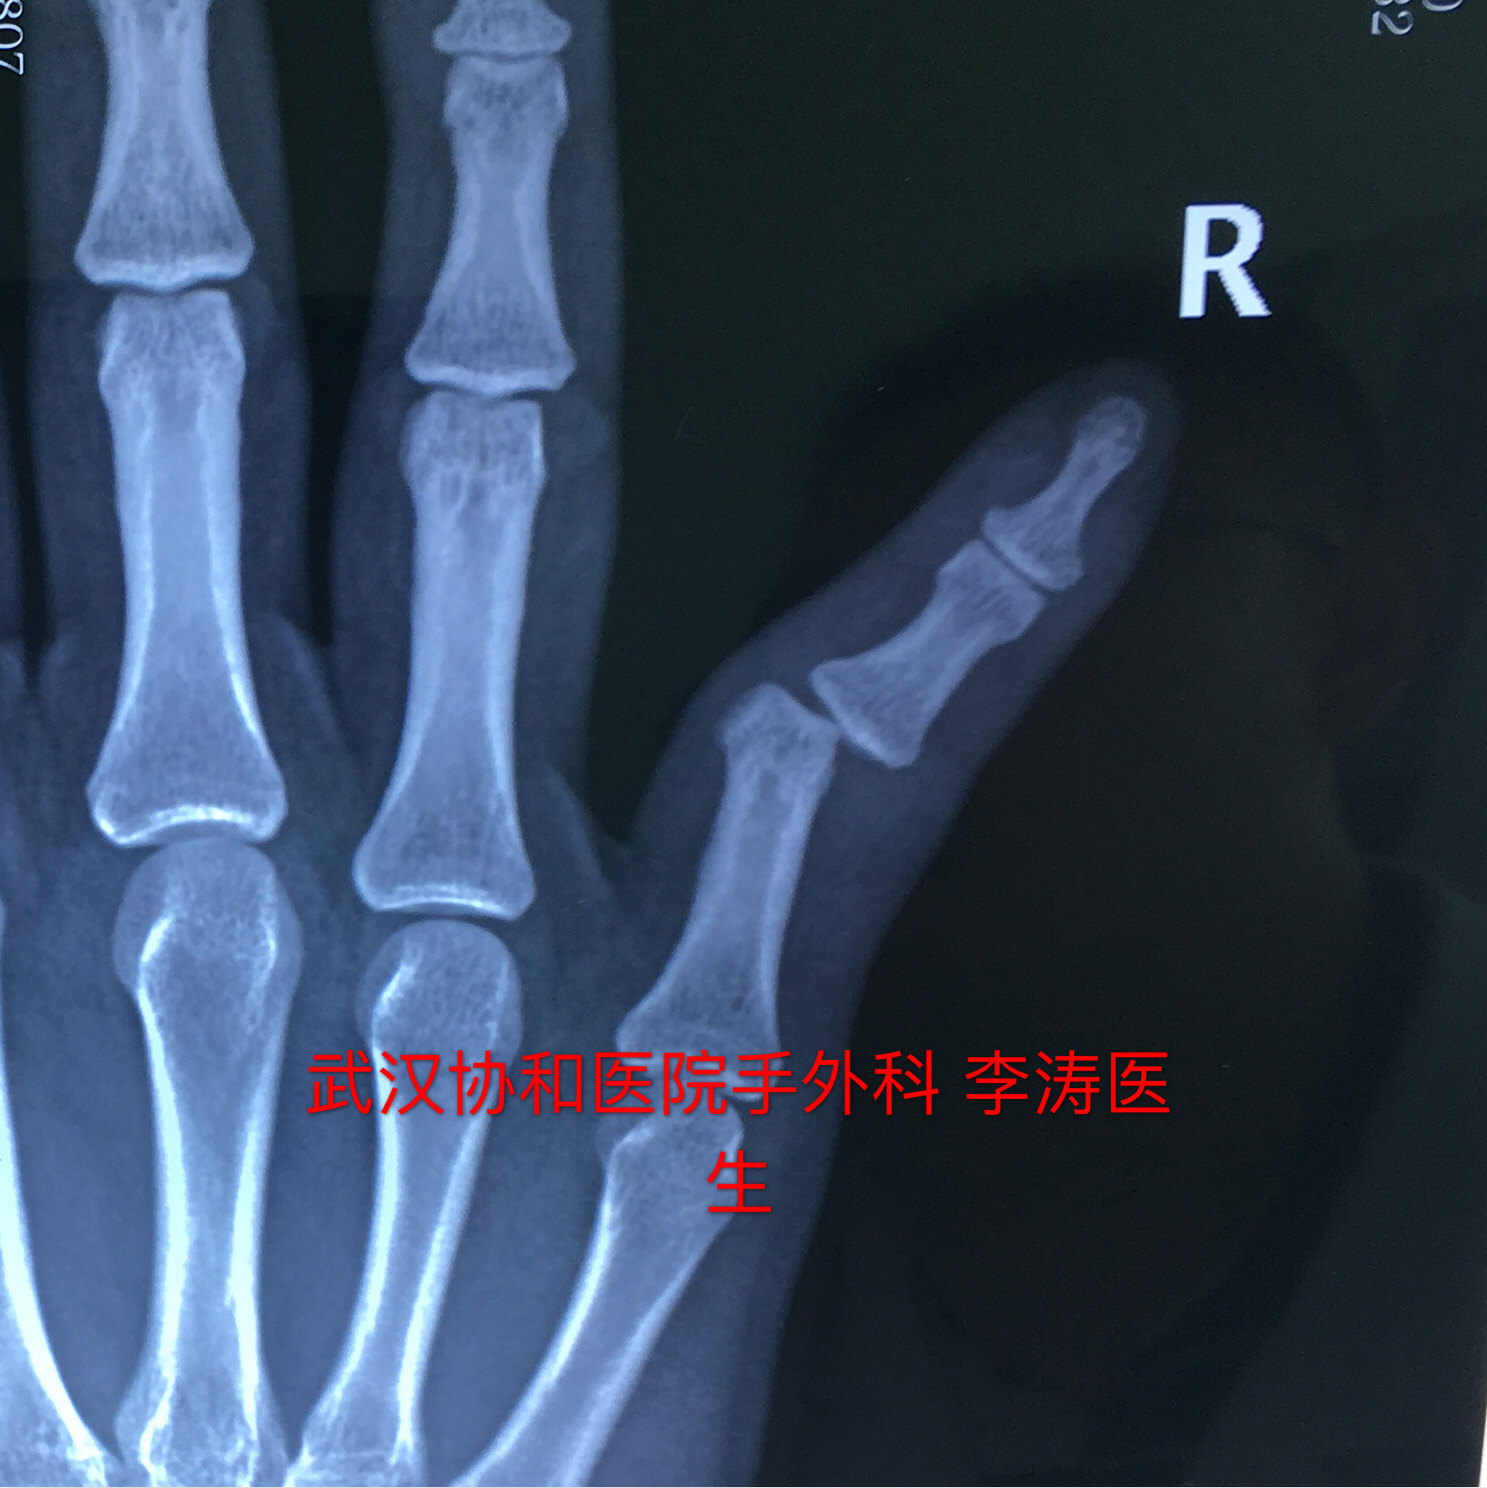

小指骨折手术-右手第五掌骨粉碎性骨折 第一个月张开手掌握拳训练 第二个月握力训练 捏网球 第三个月 感觉没什么了 就上单双杠了 附图一做完手术和三个月 —————————————————————— 这周去取了钢板,骨头上都是洞洞,同样的要恢复半年 术后一 平片提示:小指中节指骨颈部 3 型骨折。同样因闭合复位效果不满意改行手术治疗。具体过程如下。 图 2 小指指骨颈部骨折 3 型 a:正位片;b:侧位片 方法 先在透视下行闭合复位。行纵向牵引后将向背侧移位的指骨头向掌侧推挤(图 3),并保持骨折端复位。

平片提示:小指中节指骨颈部3型骨折。同样因闭合复位效果不满意改行手术治疗。具体过程如下。 图2 小指指骨颈部骨折3型。(a)正位片(b)侧位片 方法 先在透视下行闭合复位。行纵向牵引后将向背侧移位的指骨头向掌侧推挤(图3),并保持骨折端复位。你好,在战斗过程中,如果一侧手指骨折,打钢钉做手术,需要补偿精神损失和营养吗? 咨询时间: 1605 湖北 恩施州 交通事故 打架造成轻伤,小指骨折需要手术。被判刑需要多长时间 咨询时间: 湖北神农架林区劳动争议 我也要提问当前在线律师23,564位,如遇类似法律问题,立即咨询